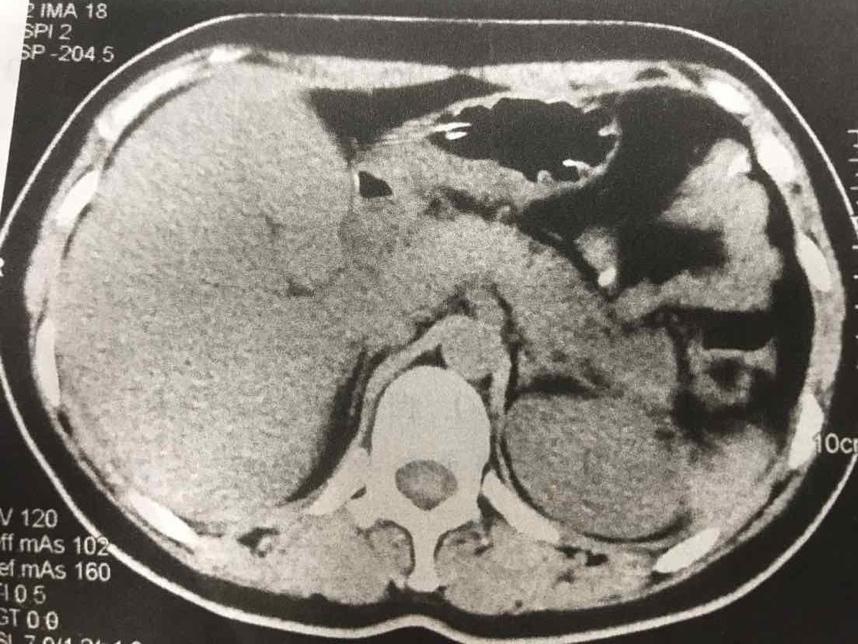

摘要:本文介紹了急性胰腺炎的最新分型,包括其分類標準和特點。文章還提到了一天的奇妙之處與急性胰腺炎分型之間的聯(lián)系,強調(diào)了及時診斷和治療的重要性。全文旨在提高人們對急性胰腺炎的認識,以便更好地預(yù)防和治療該疾病。